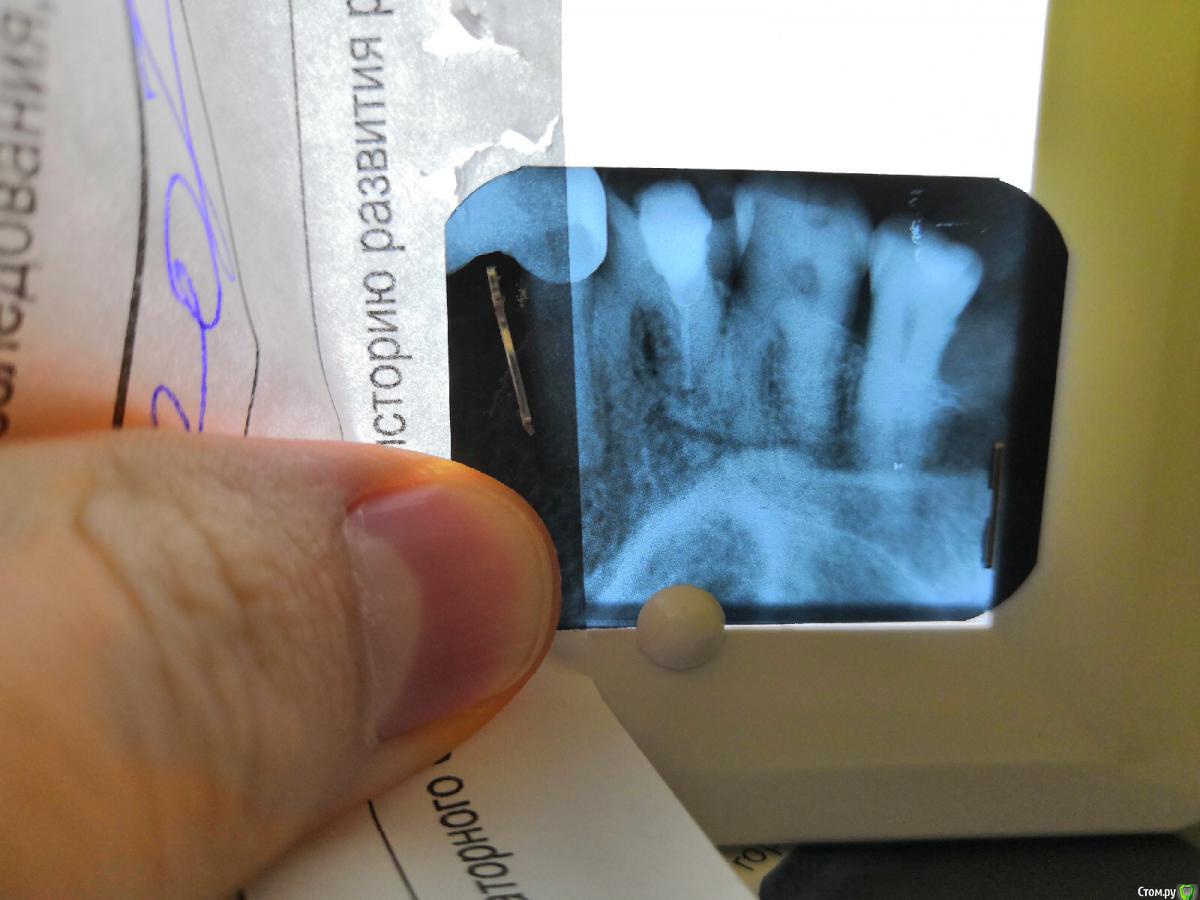

Здравствуйте не могли бы подсказать сколько вы видите каналов в зубе 2.7.Мне кажется там 2 корня(2 канала)нашёл медиально—щёчные канал и небный(расширил на периапикальный снимке Гейтсом ) дистально щёчный никак не смог найти,хотя устья других каналов были приличные(сразу обозримые и зондируемые).На другом снимке зуб 45 ,протяженность канала обрывается на границе средней и апикальный трети ,думаю там бифуркация 4аналов? или мне кажетсяpost-55917-0-65872500-1562703527_thumb.jpegpost-55917-0-21792800-1562703539_thumb.jpegpost-55917-0-24560700-1562703559_thumb.jpeg

Сделайте снимок с инструментами, не поможет - отправьте на клкт. В целом, зуб похож на обычный, т.е. 3-4 канала. 45, имхо, двухканальный, но это не точно.